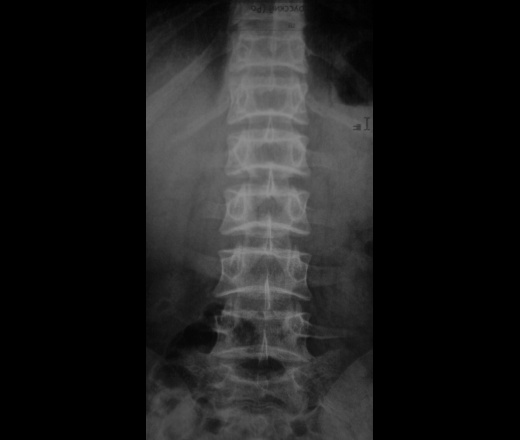

Ребенок 8 лет поступил в детское травматологическое отделение с болями в спине. На мой взгляд позвонки не нормальные. Изменены по типу рыбьих. может это вариант нормы или какая то система. Дистрофический процесс? Какие ваши мнения. и при каких состояниях, если это патология, мы можем видеть данные изменения. Буду рад полезным ссылкам)

прошу прощенья. ребенку 14 лет.

Рыбьи позвонки описывает Майкова-Строганова как результат остеопоротических изменений.(Кости и суставы в рентгеновском изображении. Туловище). БМЭ и Рейнберг такие позвонки относят к врожденным деформациям.

И еще:"Рыбьи позвонки — позвонки с двояковогнутыми краниальной и каудальной пластинками. Характерны для несовершенного остеогенеза, некоторых эндокринных спондилопатий, гемобластозов, хронического отравления солями тяжелых металлов." Э.В. Ульрих, А.Ю.Мушкин. Вертебрология в терминах, цифрах и рисунках, Спб, 2005

На счет "выпирания"дисков для меня сомнительно. При ф-х пробах все ок. Про смещения позвонков тоже недостоверно-смещение должно быть смещением(для меня). Про spina bifida - вполне согласен. Про анамнез уточню в понедельник, также про спорт и тд. Но мой главный вопрос - это двояковогнутые позвонки - норма или нет . и где предел нормы. За мнения спасибо.

И еще раскопала у себя книгу "Гормональная спондилопатия", авторы Герман и Кетрарь. При этой патологии формируются сначала "рыбьи позвонки", затем остеопроз приводит к патологическим переломам. Плюс куча всякой сопутствующей гадости. И отдельно выделена гиперпаратиреоидная дистрофия- болезнь Реклингаузена.

Если это ребенок, то скорее всего рыбьи позвонки результат дисплазии

Нормальным может быть "слегка вогнутая" поверхность тел позвонков в боковой проекции. Но не "столь вогнутая", как в данном случае. Тем более, что к 14 годам все уже почти как у взрослых. Вывод однозначен - не норма.